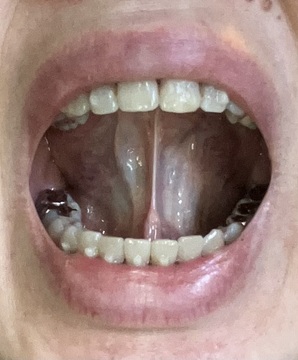

舌に歯型ついていて、朝起きたら顎に痛みがある